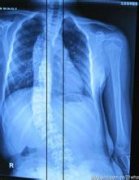

强直性脊柱炎的危害大家可能仅仅认为会使人腰酸背痛浑身难受,然而却不知道如果强直性脊柱炎不及时治疗的话很可能导致人的残疾。因此我们必须要认真对待它,不能有丝毫的马虎。那么要 如何才能降低强直性脊柱炎的致残率 呢,现在就让贵阳强直性脊柱炎医院的...[详细] 2016-03-14

强直性脊柱炎在我们的生活中也算比较常见的疾病了,然而许多患者并不重视这些疾病的治疗,导致疾病发展到后期越来越严重,也超出我们身体的负荷,才知道严重性。那么 强直性脊柱炎不治疗会带来哪些危害 呢?我们请贵阳强直性脊柱炎医院的专家来为大家介绍吧:...[详细] 2016-03-10

患上强直性脊柱炎并不是十分可怕的一件事。如今有发达的科学技术,治疗这类疾病不再是梦想。如今的治疗技术有很多,而且许多强直患者都表现出骨头坏死的迹象,那么强直性脊柱炎骨头坏死怎么办呢?我们请 贵阳强直性脊柱炎医院 的专家来为大家介绍一下吧: 强...[详细] 2016-03-07

强制性作为一种风湿骨科类疾病,一旦患上将会十分痛苦,如果不及时治疗,或者不配合治疗将会造成会严重的后果。这并不是危言耸听,现在就让我们来了解了解强直性脊柱炎治疗不及时会有怎样的后果。请 贵阳强直性脊柱炎医院 的专家来为大家介绍吧: 在强直性脊...[详细] 2016-03-04